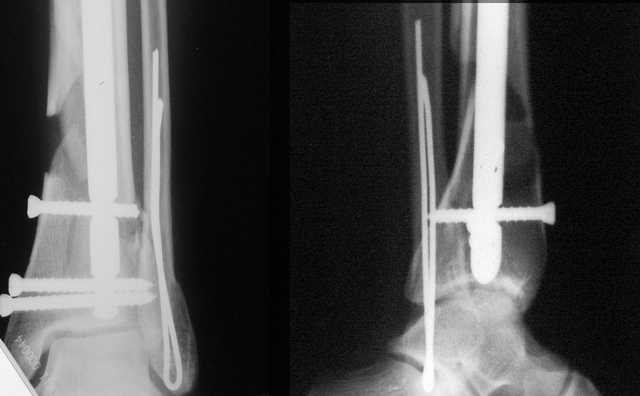

В приложении остеосинтез перелома шейки плеча LPHP у доктора из нашей клинике , через 8недель уже трудился в операционной

Кликните для загрузки файла 06.JPG

АМ> В приложении остеосинтез перелома шейки плеча LPHP у доктора из нашей

АМ> клинике, через 8недель уже трудился в операционной

Очень симпатично, спору нет, но полагаю, что и с Y-спицами полная реабилитация к этому сроку была бы вполне реальна.